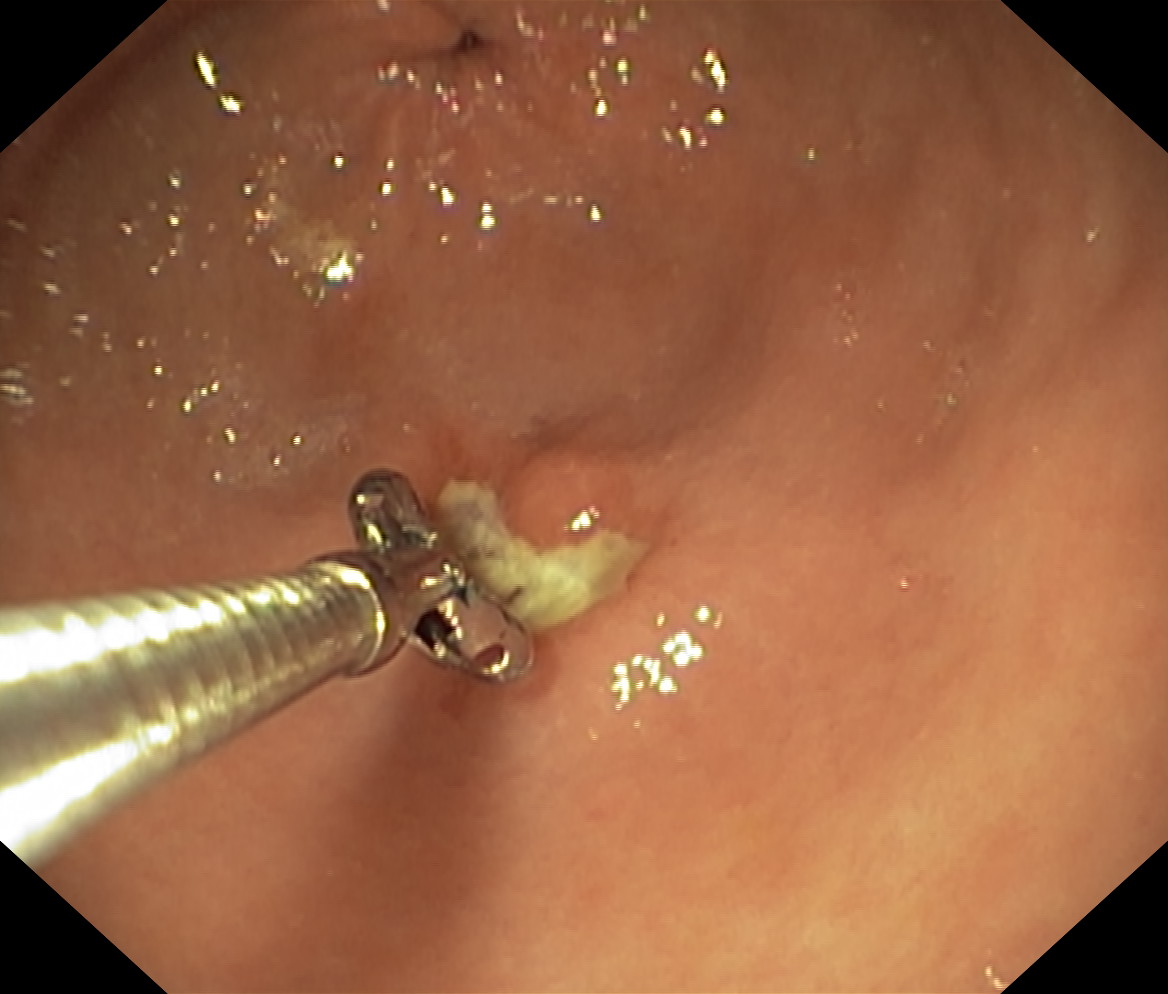

Wrzód trawienny